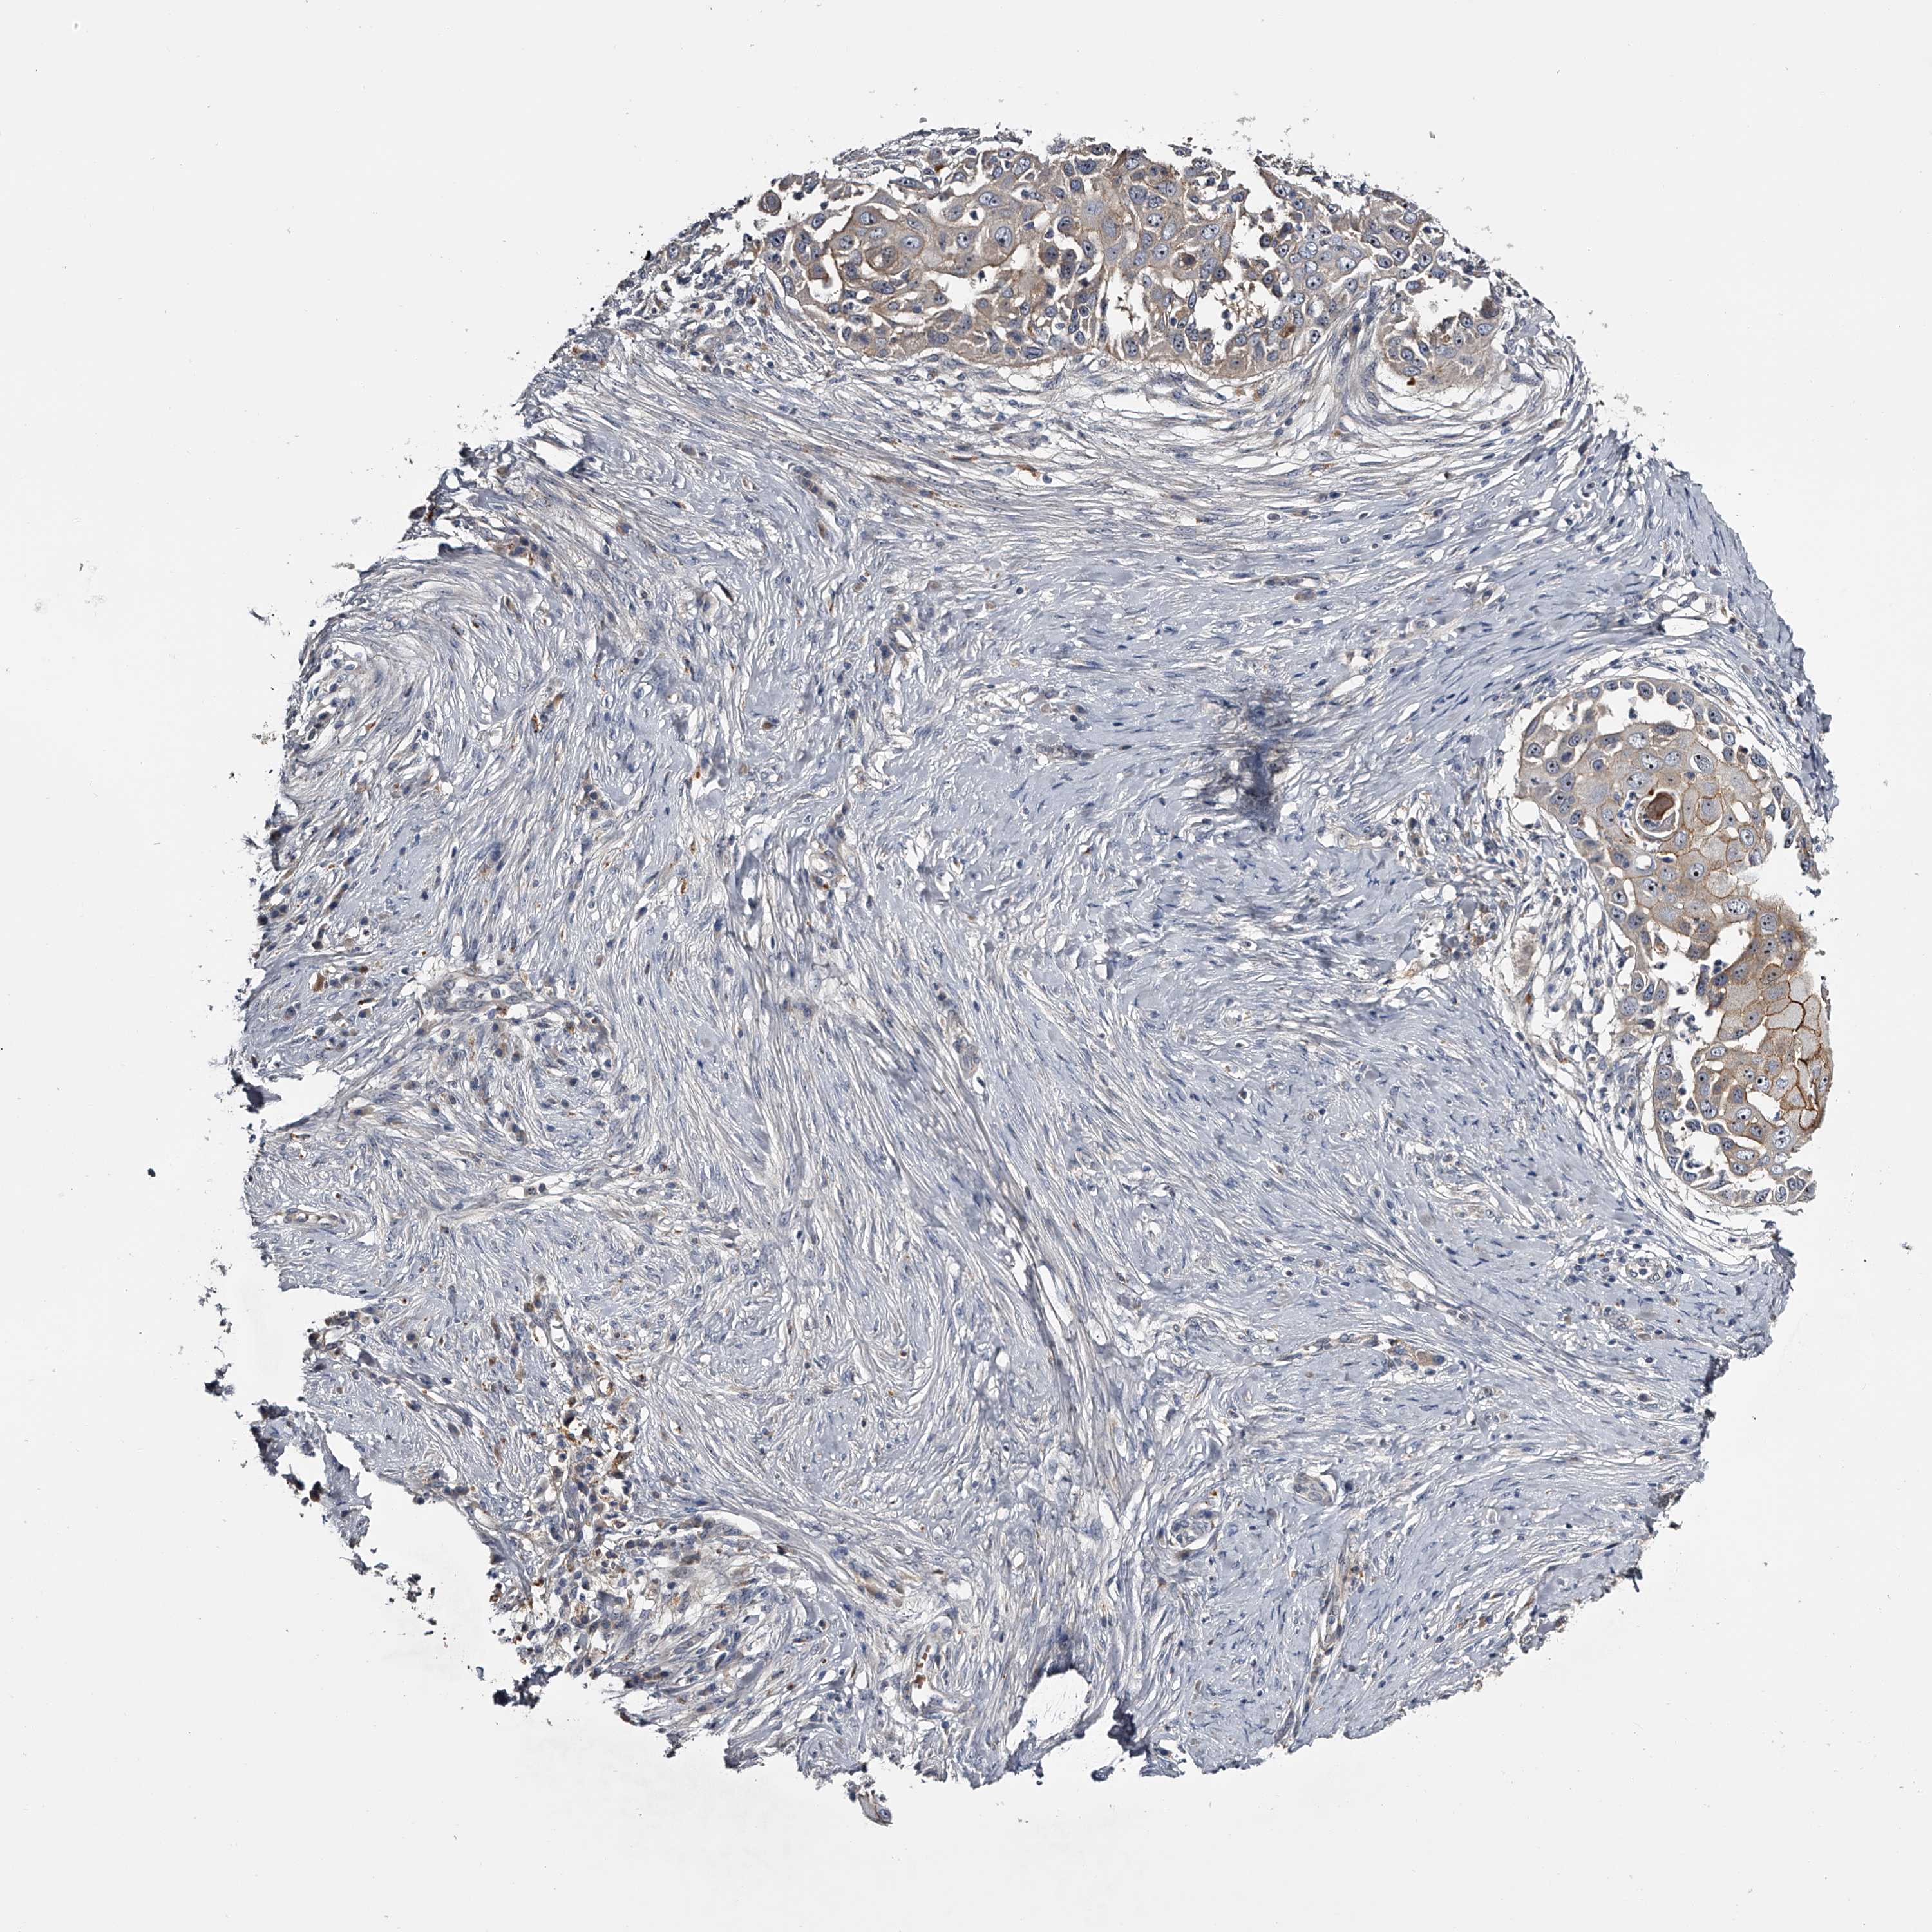

SKIN CANCER - Protein expressioni

A mouse-over function shows sample information and annotation data. Click on an image to view it in a full screen mode. Samples can be filtered based on level of antibody staining by selecting one or several of the following categories: high, medium, low and not detected. The assay and annotation is described here.

Each image is clickable and will lead to virtual microscopy that enables deeper exploration of all samples and also displays staining intensity scores, fraction scores and subcellular localization as well as patient and tissue information for each sample.

Antibody HPA029666

Antibody HPA029667

Antibody HPA029668

Antibody HPA029669

Basal cell carcinoma

Squamous cell carcinoma, NOS

Squamous cell carcinoma, metastatic, NOS